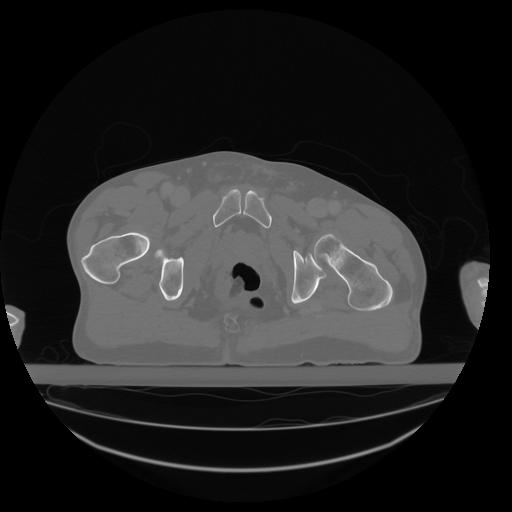

34 CUERPO,CE,Vol,1.0,CUERPO,,